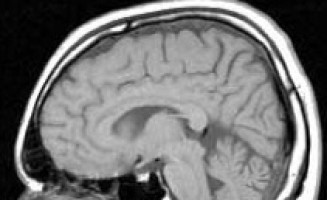

El glioblastoma es una forma grave de cáncer cerebral, con un pronóstico muy pobre.

Cada vez es más evidente que los tumores de glioblastoma contienen muchas aberraciones genéticas que varían entre los pacientes.